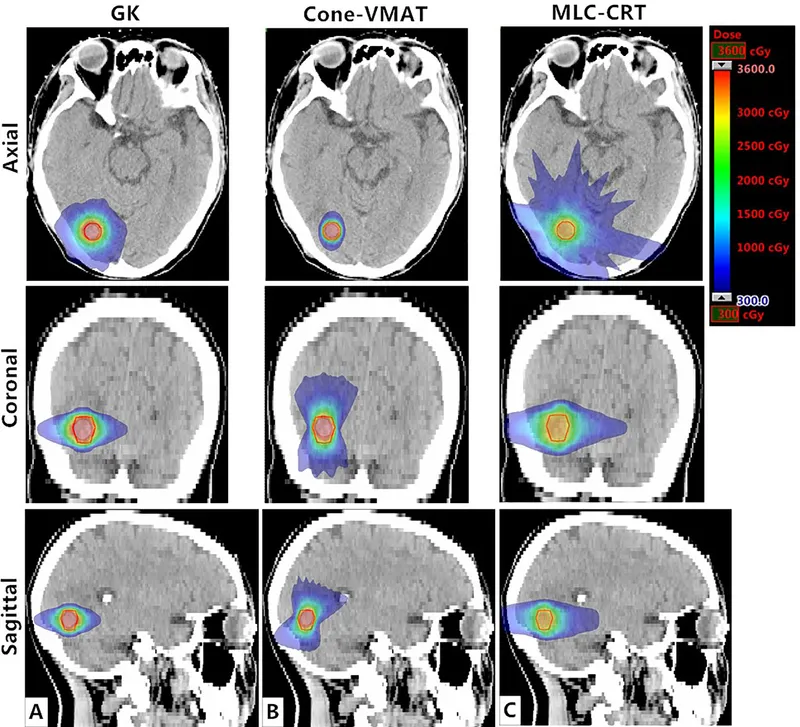

- Gamma Knife (GK): Multiple Cobalt-60 sources (e.g., 192, 201). Intracranial. Highly conformal.

- LINAC-based SRS: Linear accelerators.

- Techniques: Conformal arcs, Dynamic Conformal Arcs (DCA), IMRS.

- Conformality: Radiation dose is meticulously shaped to closely match the 3D contour of the target volume.

- Steep Dose Gradient: Achieves a rapid decrease in radiation dose at the periphery of the target, minimizing exposure to adjacent healthy tissue.